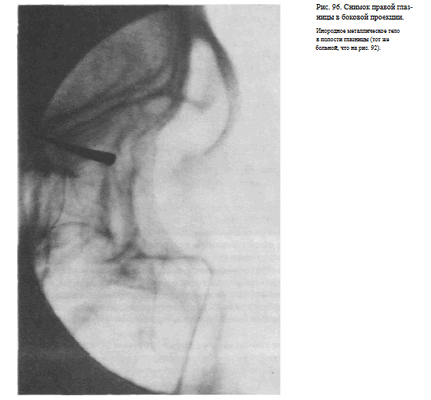

СНИМОК ГЛАЗНИЦЫ В БОКОВОЙ ПРОЕКЦИИ

Назначение снимка — отображение наружного края, верхней и нижней стенок глазницы, а также выявления инородных тел, находящихся в ее полости.

Укладка больного для выполнения снимка такая же, как для выполнения снимка черепа в боковой проекции (рис. 95).

Кассету размером 13X18 см устанавливают в кассетодержателе в поперечном положении. Наружный край глазницы соответствует центру кассеты, и на него направляют пучок излучения.

Информативность снимка. На снимке хорошо видна наружная стенка глазницы. Для выявления небольших участков измененной костной структуры других стенок информативность снимка, как правило, невысокая из-за суперпозиции анатомических образований противолежащей стороны лицевого скелета. Хорошо видны на снимке в данной проекции инородные тела (рис. 96).

Критерии правильности технических условий съемки и правильности укладки. Правильность подбора физико-технических условий съемки определяется резкостью изображения контуров костей и четкостью костной структуры.

При правильной укладке контуры верхней и нижней стенки правой и левой глазницы совпадают.